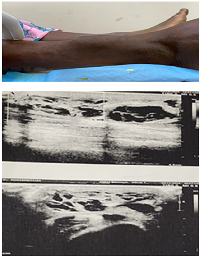

Examination revealed a firm, non-tender, relatively immobile swelling measuring approximately 6 × 5 cm, located on the anterior aspect of the lower third of the right leg. The overlying skin appeared normal, without redness, hyperpigmentation, ulceration, or prominent superficial veins. No regional lymphadenopathy was detected. Routine hematological parameters were within normal limits. Ultrasound of the swelling showed a well-defined, hypoechoic, cystic lesion measuring 6.8 × 5 cm containing internal echoes consistent with blood, suggestive of an organized hematoma (Figure 1). Fine-needle aspiration cytology (FNAC) yielded red blood cells, further supporting this initial impression.

Soft tissue EHE is diagnostically challenging because its clinical and radiologic presentation often mimics benign entities such as organized hematomas, lipomas, or cystic lesions. USG usually shows discrete hypoechoic lesion and MRI also shows low signal intensity lesions on T1W images and heterogeneous high signal intensity on T2W sequences [7].

In the present case, ultrasonography demonstrated a well-defined hypoechoic lesion containing blood, suggestive of an organized hematoma, while MRI revealed a lobulated, multiloculated lesion with T1 isointensity and heterogeneous T2/STIR hyperintensity. Such overlap is a recognized pitfall in EHE diagnosis, as the tumor’s vascular nature may not produce the aggressive radiologic features typically expected in malignant lesions. This explains why FNAC, which yielded only red blood cells, also failed to identify the neoplastic nature of the lesion.